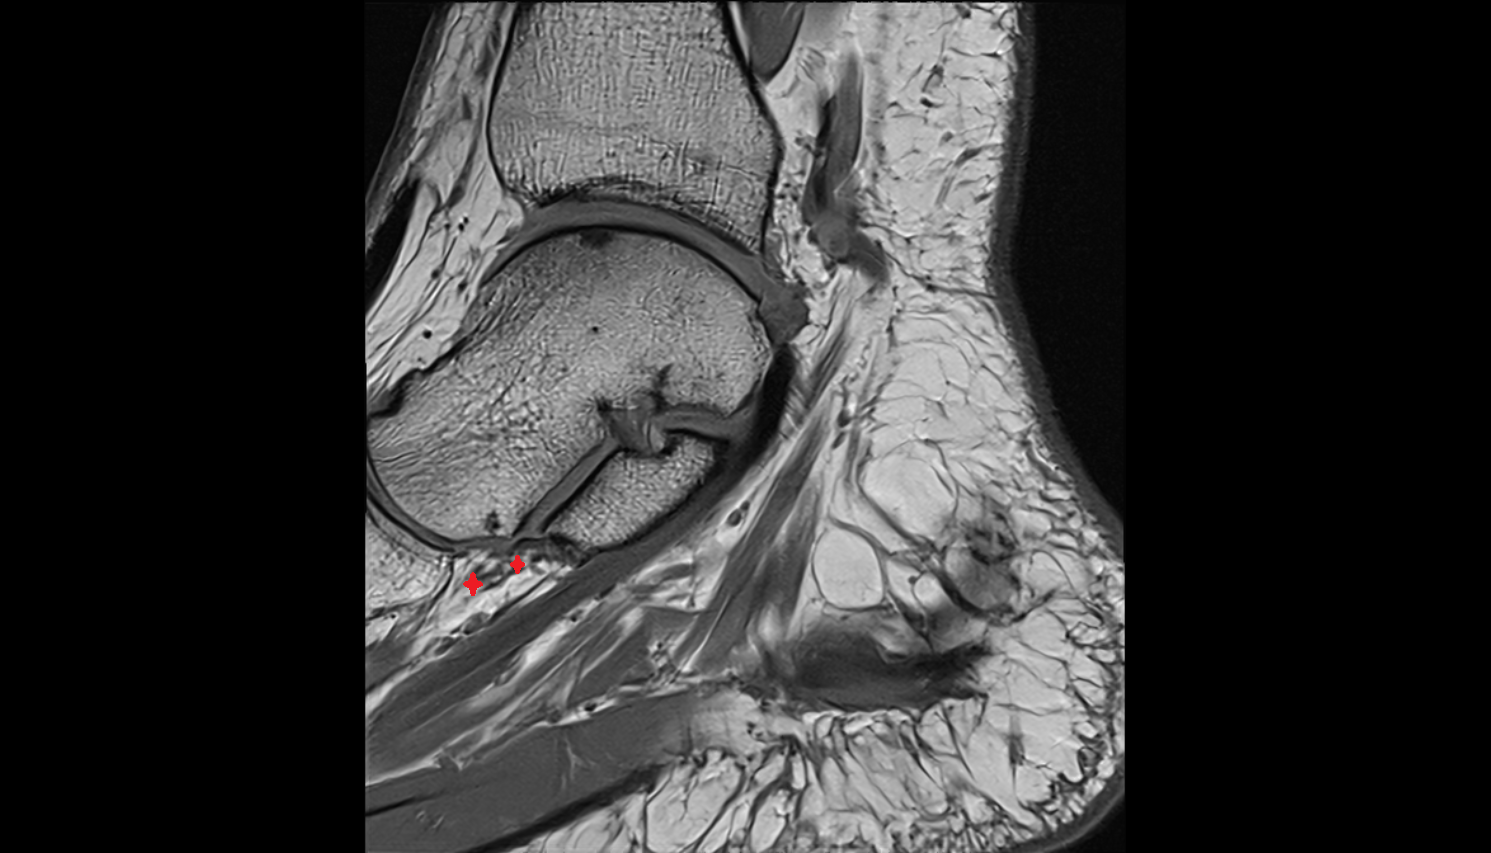

- Achilles tendon

- Anterior talofibular ligament

- Posterior talofibular ligament

- Deltoid ligament complex

- Talocalcaneal interosseous ligament

- Kager fat pad (pre-Achilles fat pad)